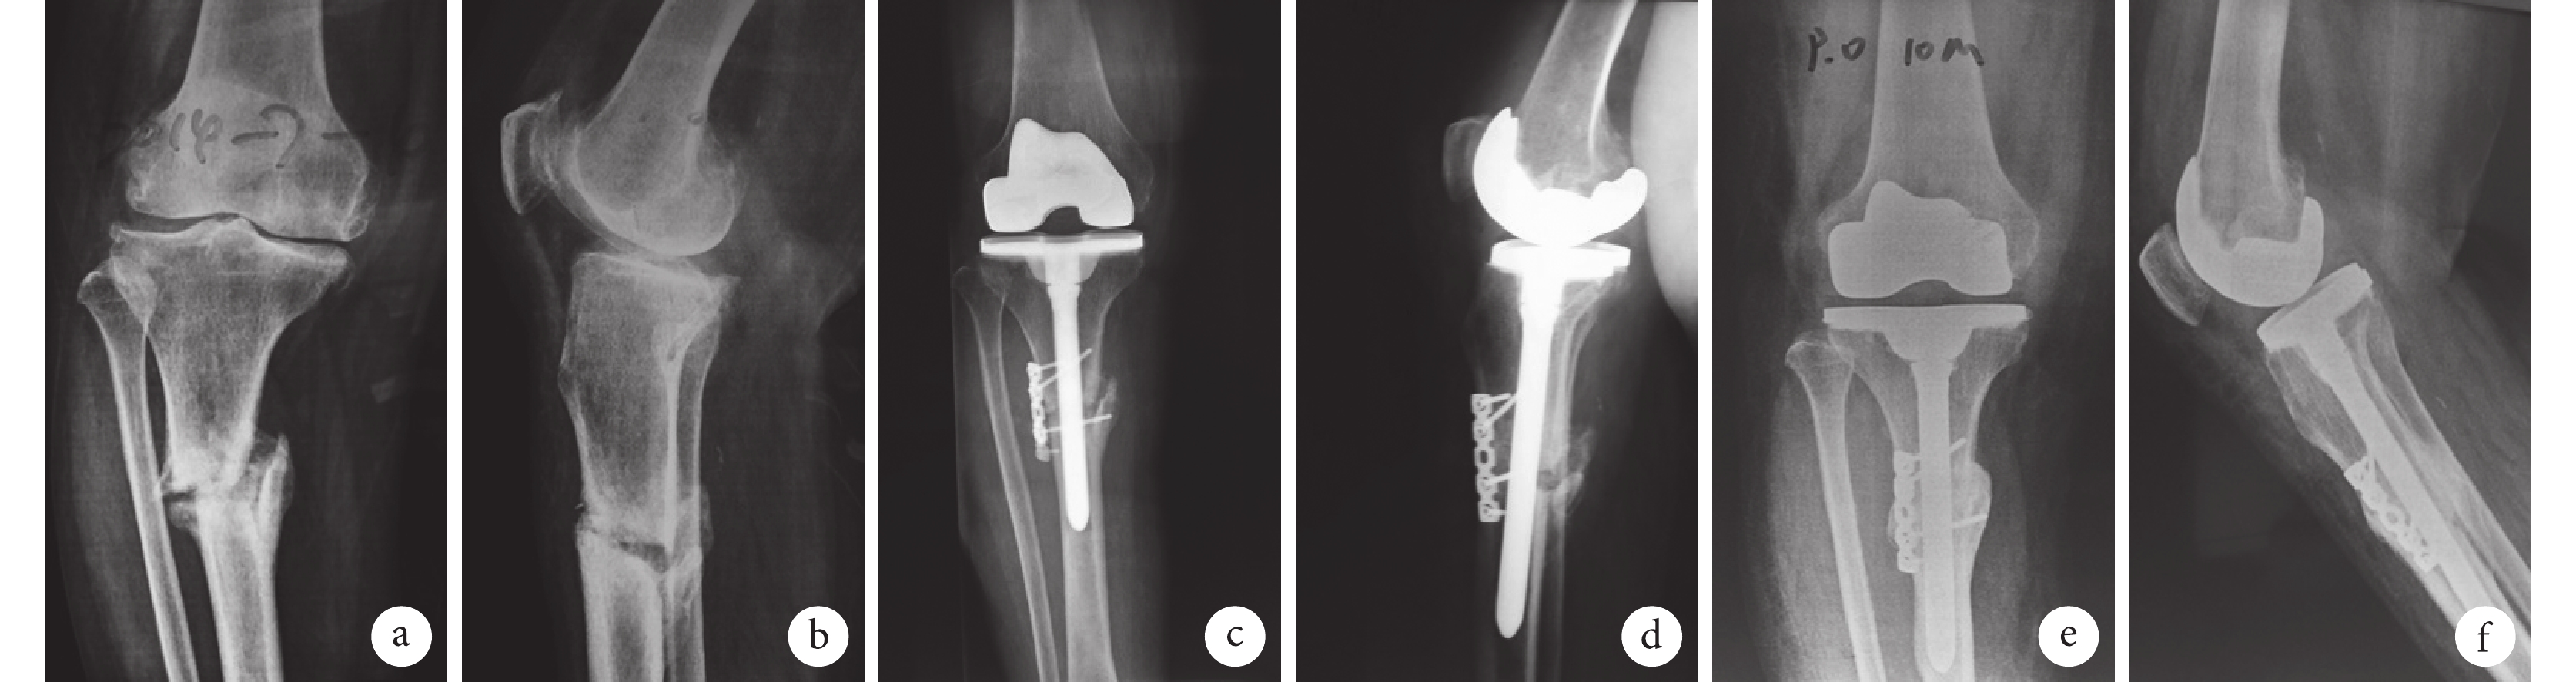

a、b. 術前;c、d. 術后即刻;e、f. 術后10個月

Figure1. X-ray films of a 60-year-old female patient with right knee arthritis and tibial stress fracturea, b. Before operation; c, d. At immediate after operation; e, f. At 10 months after operation

術后切口均Ⅰ期愈合。12 例患者均獲隨訪,隨訪時間 6~52 個月,平均 36.5 個月。X 線片復查示,脛骨骨折均愈合,愈合時間 3~7 個月,平均 4 個月;其中 3 例關節外骨折術中行切開斷端清理者,骨折延期愈合,術后 7 個月左右愈合。末次隨訪時,均無假體松動及假體周圍骨溶解、關節不穩定等并發癥發生。見圖 1。膝關節內翻畸形糾正,末次隨訪時膝關節 KSS 臨床評分(90.5±8.9)分、功能評分(92.1±7.8)分,膝關節活動度(115.0±9.8)°;均較術前明顯改善,比較差異有統計學意義(t=40.340,P=0.000;t=32.120,P=0.000;t=8.728,P=0.000)。